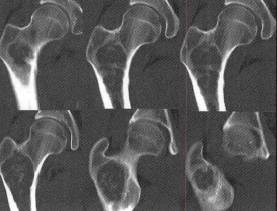

图1右股骨内生软骨瘤

C.D.CT轴位骨窗和冠状位MPR见右股骨干骺端有一卵圆形低密度肿块影,呈中心性,肿块周围见高密度硬化边,内部见斑点状、斑片状钙化,骨皮质完整无破坏